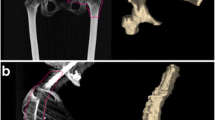

The vertebral bodies T10–L5 were manually segmented using three-dimensional volumes of interest (VOIs) on axial, sagittal, and coronal reconstructed bone marrow CT images. Areas next to the cortical bone, larger bone marrow vessels (e.g., the basivertebral vein and its bony canal) as well as focal lytic lesions, and areas of bony sclerosis were carefully excluded (Fig. 1). Focal lesions which had to be excluded from segmentation are summarized in Table 1. The segmentations were performed by three readers in consensus in a blinded fashion. Two of the readers were radiologists with 30 years and 4 years of experience in diagnostic imaging. For assessment of reliability, segmentations were additionally performed by two readers independently following feature extraction.

Unenhanced DECT for post-processing and generation of non-calcium “bone marrow image data” which were used for manual segmentation of the vertebral bodies T10–L5. Areas next to the cortical bone, larger bone marrow vessels (e.g., the basivertebral vein and its canal), and focal lytic lesions were excluded